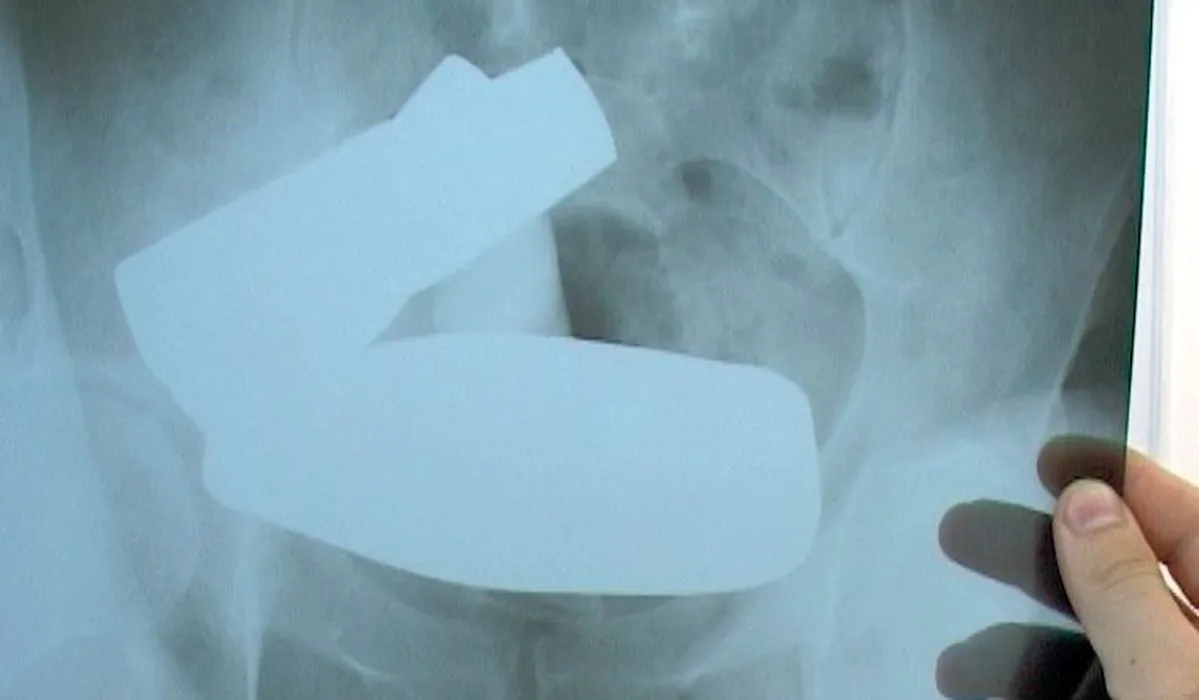

Un bărbat s-a prezentat la doctor cu o problemă neobișnuită / Consultat de urgență, pacientul a fost nevoit să recunoască adevărul șocant. Chirurgii care l-au salvat au rămas uimiți: „A spus inițial că a căzut în ea…”